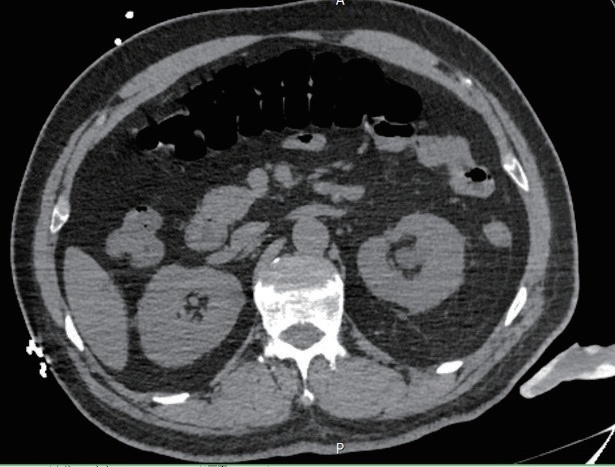

根据检查结果,最终以“泌尿系 CT 示左侧输尿管腹段结石(直径3mm)伴左肾盂积水及上段输尿管扩张”的诊断将侯先生收入住院,并告知家属侯先生的病情是十分危险的。

像上述文章里提到的侯先生就是尿源性脓毒血症最典型的症状,有高烧、寒战这些情况。泌尿系CT平扫示左侧输尿管腹段结石伴左肾盂及上段输尿管积水。考虑尿路梗阻感染引起的脓毒血症休克。